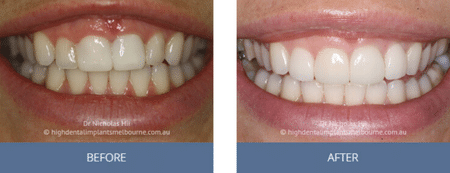

Clinical Before and After Photos

At High Dental, we believe a great smile changes everything. Our Smile Gallery showcases before-and-after images of patients who trusted us with their smiles. From veneers and crowns to full-arch implants, each result is unique — and each started with a consultation. Scroll through and imagine the possibilities for your own smile.

Before & After Disclaimer:

Images are provided for illustrative purposes only. Results shown relate to specific patients and individual outcomes may vary. A consultation is required to determine suitability for treatment.